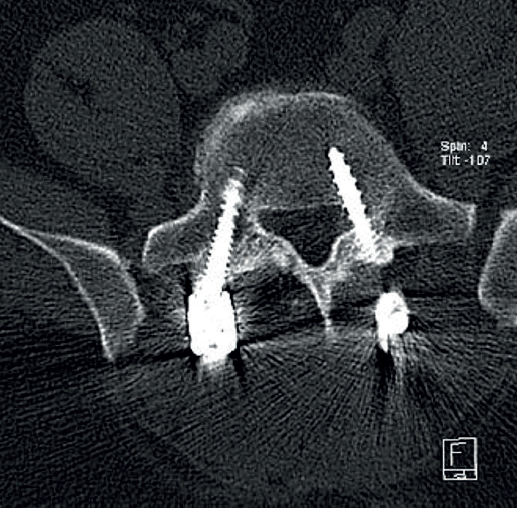

Cincuenta días tras el accidente se realizó fusión lumbar instrumentada L4-L5 con inserción de dispositivo intersomático por vía transforaminal derecha. En el segundo día postoperatorio presentó empeoramiento del dolor, objetivándose en la tomografía computarizada (Figura 2) malposición del tornillo L5 izquierdo que invadía el canal. Se reintervino a los 5 días corrigiendo el trayecto del tornillo. Sin embargo, persistió el dolor. La revaluación del caso, sumada a los hallazgos de EMG, motivó estudios complementarios de pierna y trayecto ciático (Figuras 3 y 4), detectándose una masa tumoral en el fémur izquierdo compatible con sarcoma fusocelular.

retla.08216.fs2508016-figura4.png

Figura 4. Resonancia magnética del fémur izquierdo. A: corte coronal en secuencia STIR, con masa de partes blandas de gran tamaño con afectación diafisaria femoral; B: corte axial en secuencia T2, con masa heterogénea con áreas de necrosis central; C: corte axial en secuencia T1 con supresión grasa, con compromiso del trayecto del nervio ciático por la masa tumoral.